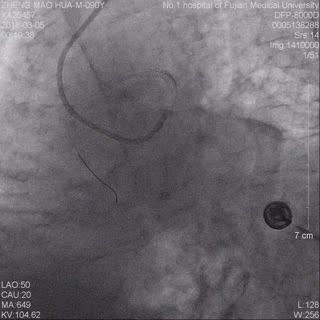

术前冠脉造影提示前降支近端急性闭塞 术后冠脉造影提示前降支血流通畅